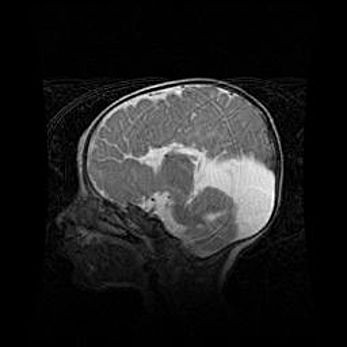

Мальформация Денди-Уокера. Киста задней черепной ямки.

Агенезия мозолистого тела.

Возраст: 2,5 месяца

Вес: 2420 г

Пол: женский

Окружность головы: 37 см

Срок гестации: 32 недели

Мальформация Денди—Уокера — редкий вид патологии ЦНС, представляющий собой врожденный порок развития каудального отдела ствола и червя мозжечка, ведущий к неполному раскрытию срединной (Мажанди) и латеральных (Лушка) апертур IV желудочка мозга. Для этогно синдрома характерна триада симптомов: гипотрофия червя мозжечка и/или полушарий мозжечка, кисты задней черепной ямки, гидроцефалия различной степени. В 70% случаев порок сочетается и с другими аномалиями головного мозга, в частности с агенезией мозолистого тела.